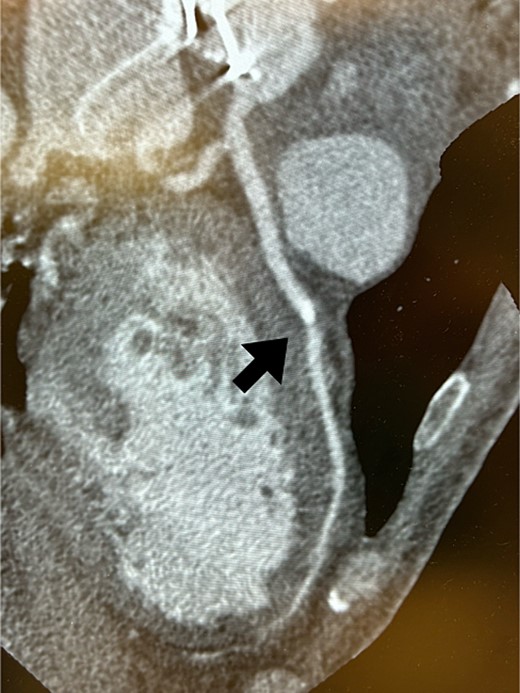

Postoperatively, an electrocardiogram revealed anterior ST-segment elevation, indicative of myocardial ischaemia. The patient then developed renal insufficiency. Given his haemodynamic stability, he was initially managed using coronary dilators and heparin. To improve renal function, coronary angiography was performed on the 10th postoperative day, which revealed a filling defect and 90% stenosis in the LAD artery (Fig. 1). Computed tomography (CT) revealed a high-density mass in the LAD artery with a mean CT value of 400 Hounsfield units (HUs) (Fig. 2). These findings indicated embolism, possibly due to a pledget from a previous surgery. A transcatheter approach was employed to remove the embolus, which was successfully extracted using a snare (Fig. 3a). Angiographic assessment revealed that the previously stenotic LAD demonstrated full perfusion, consistent with a thrombolysis in myocardial infarction (TIMI) flow grade of 3 (Fig. 3b). The patient recovered from catheterization without complications.

Coronary CT scans revealed a high-density area (arrow) in the LAD artery.

In this case, we were able to predict preoperatively that embolization was caused by a pledget. First, the embolus revealed 400 HU on the coronary CT. The causes of embolism after cardiac surgery include blood clots, soft plaques on the arterial wall, and intraoperative use of haemostatic agents. The most frequently reported cases are postoperative embolisms caused by Bio-glu [3, 5–7]. In this case, the 400 HU presented by the embolus was clearly higher than that presented by Bio-Glu. Second, it had a square shape with rounded corners on coronary angiography, suggestive of a manufactured object. These findings suggested that the embolus was an artificial embolism and not due to bio-glue. We inferred that it was a pledget from the previous surgery. CT scan and coronary angiography are useful for estimating the causes of emboli.